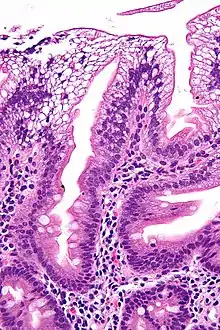

Există o absență de apolipoproteină B. Pe biopsia intestinală, vacuolele care conțin lipide sunt observate în enterocite. Această tulburare poate duce, de asemenea, la acumularea de grăsime în ficat (steatoza hepatică). Deoarece celulele epiteliale ale intestinului nu au capacitatea de a plasa grăsimile în chilomicroni, lipidele se acumulează la suprafața celulei, aglomerarea funcțiilor necesare pentru o absorbție adecvată.